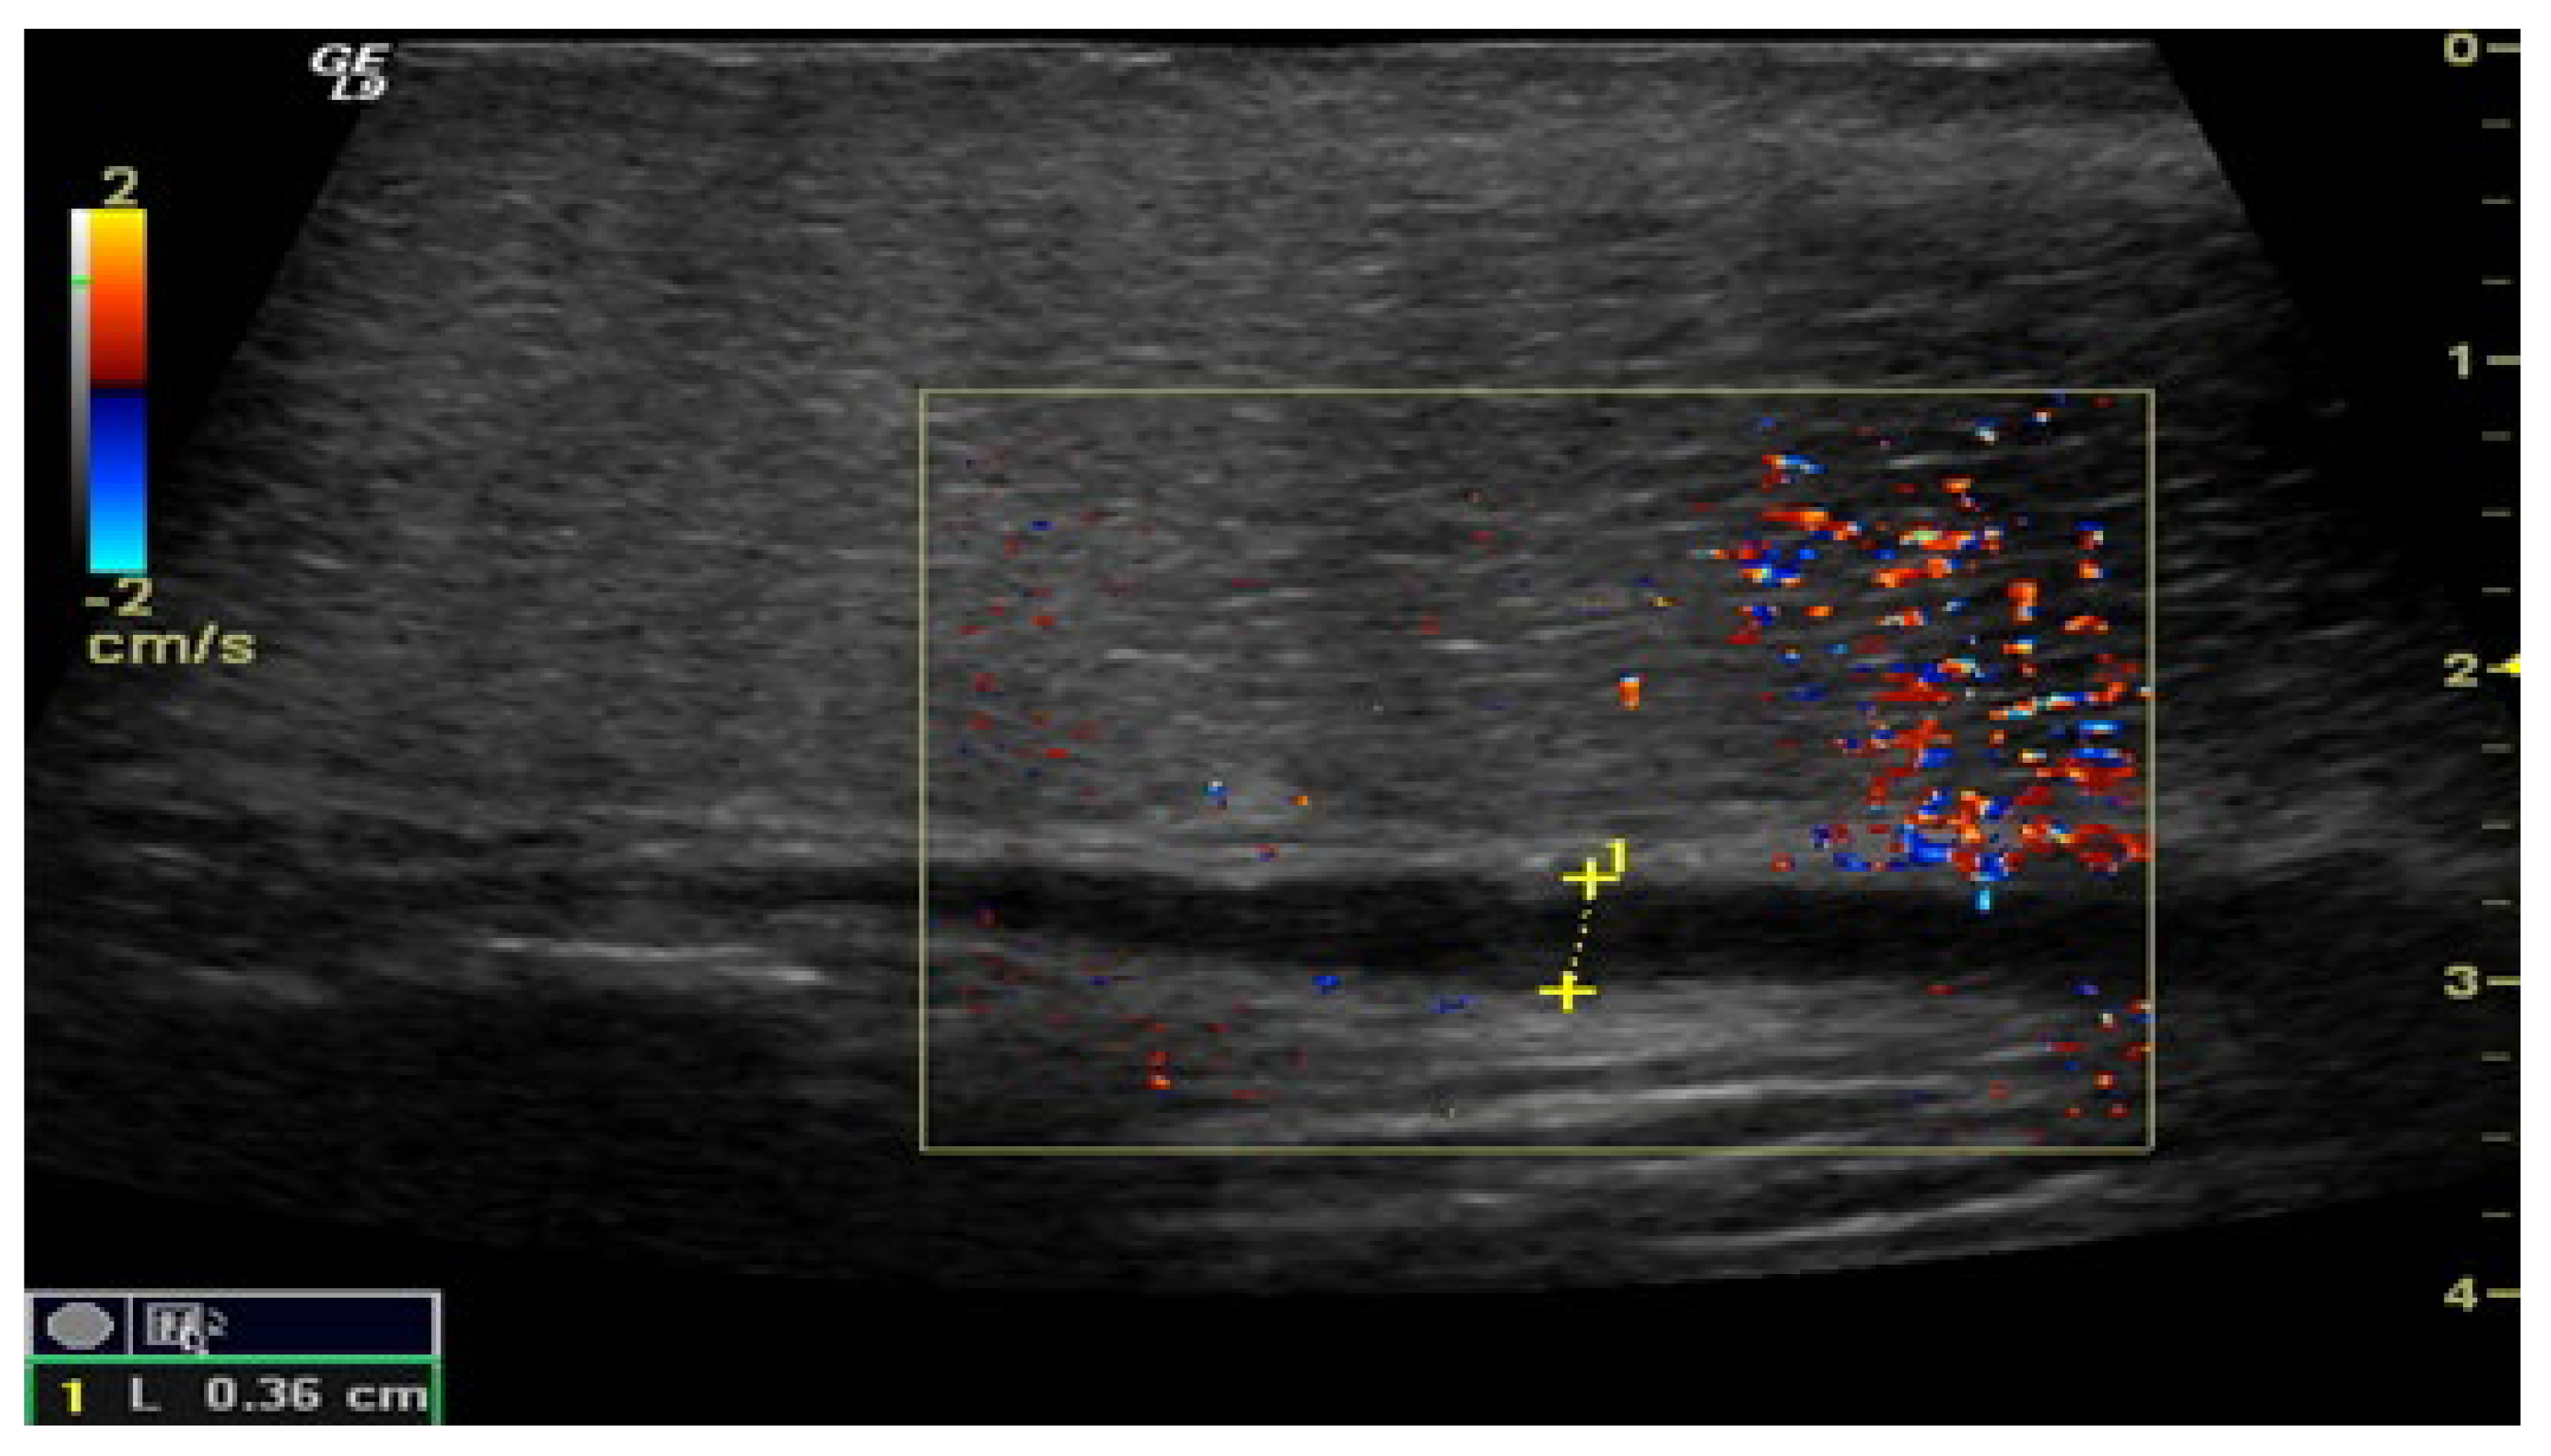

The penile CDUS revealed that 50 (56.8%) patients had ED signs, and 38 (43.2%) patients had no structural changes. Among these fifty males, 22 (25%) patients had penile arterial insufficiency (Figure 2), 17 (19.3%) patients had veno-occlusive ED (Figure 3), and 11 (12.5%) men had microcirculation disorder in the cavernous bodies of the penis (χ2 = 10.68, p = 0.002). Thus, the odds of detecting ED by using pharmacologically stimulated CDUS are 2.00 (OR = 4.47; 95% CI: 1.77 to 11.24).

Figure 3. Penile CDUS during pharmacologically induced erection. Signs of veno-occlusive ED: diameter of the deep dorsal vein is enlarged, indicating venous insufficiency.